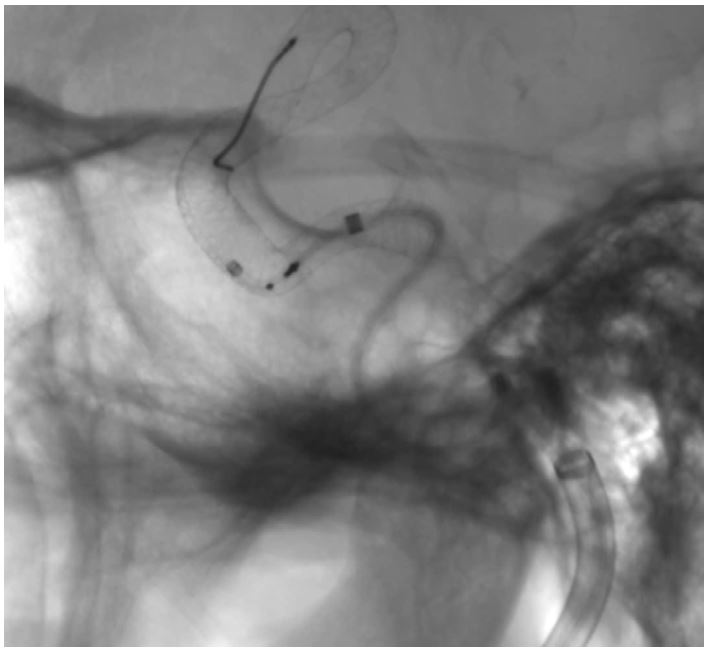

Малюнок 2: Демонструється отримання рентгеноскопічного зображення PED,  на FOV 8x8 см у HD режимі, PED використовується для лікування лівої кавернозної аневризми ВСА. Розташування PED на стінці судини можна точно оцінити за допомогою введеного контрасту на останньому зображенні.

Процедури інтервенційної нейрорадіології продовжують зростати в обсязі та складності, випробовуючи навички нейроінтервенціоналістів. Тематичні дослідження від Nagesh1 демонструють успішну інтеграцію системи в їх рутинну клінічну практику, а також надають зворотній зв'язок про те, як зображення високої роздільної здатності дозволяє їм визначати пріоритетність клінічних рішень і результатів пацієнтів, буквально відточуючи нюанси їх індивідуальних особливостей. Автори показують, як у разі розгортання PED (pipline embolization device) для лікування внутрішньочерепної аневризми, детектор високої чіткості дозволяє їм точніше візуалізувати структурні зміни PED, що впливає на їх клінічні рішення під час процедури.

В іншому випадку режим високої чіткості також використовувався для кращої візуалізації прилягання стента до стінки судини, що не тільки вплинуло на прийняття рішень, а ще й на довгострокові результати для пацієнтів.